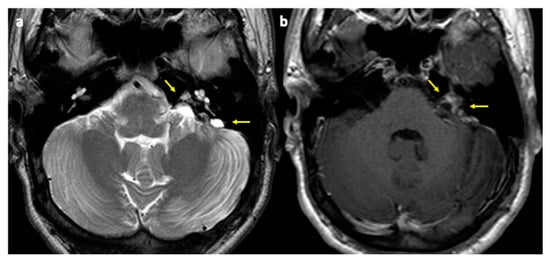

2. Case Report